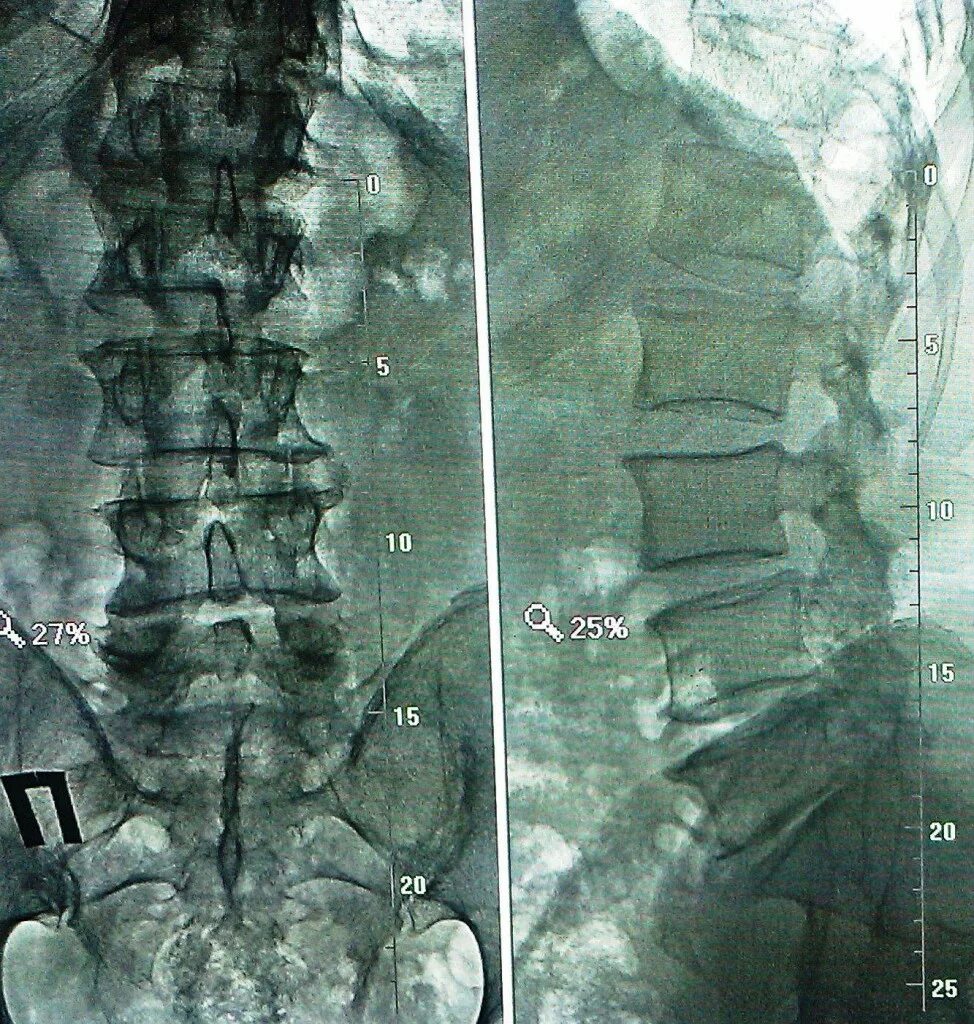

Остеохондроз l5 s1 дисков